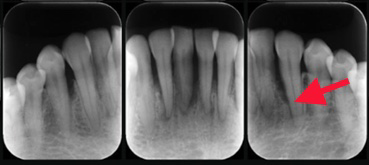

では実際の患者様のレントゲン写真をご覧ください。

この方は、骨格的にも歯並びにも特に目立つ問題がなく、むし歯もできにくかった為、長年歯医者に行かなくても日常生活に支障がでませんでした。

最近、下の前歯の歯茎から膿が出てきた事をきっかけに来院されました。

それでは詳細のレントゲンで骨の状態を確認していきましょう。赤の矢印が骨の位置を示しています。

初診時